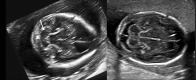

The advance in the imaging tools during the pregnancy (ultrasound and magnetic resonance) allowed the early diagnose of many fetal diseases, including the neurological conditions. This progress brought the neurosurgeons the possibility to propose treatments even before birth. Myelomeningocele is the most recognized disease that can be treated during pregnancy with a high rate of success. Additionally, this field can be extended to other conditions such as hydrocephalus and encephaloceles. However, each one of these diseases has nuances in the diagnostic evaluation that should fit the requirements to perform the fetal procedure and overbalance the benefits to the patients. In this article, the authors aim to review the neurosurgical aspects of the antenatal management of neurosurgical conditions based on the experience of a pediatric neurosurgery center.